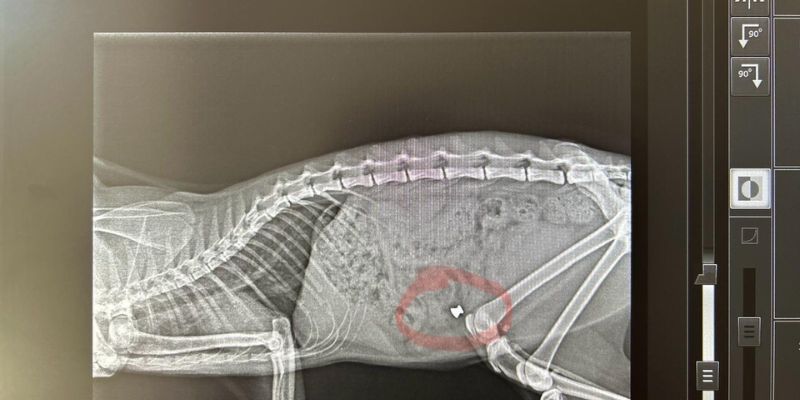

Nel quartiere popoloso di contrada Tivolille, proprio in mezzo alle abitazioni, persone non identificate stanno utilizzando fucili ad aria compressa per sparare ai gatti, utilizzando proiettili di piombo che variano da 4,5 a 6 mm, probabilmente modello diablo. La situazione è estremamente preoccupante, con alcuni gatti che sono stati uccisi e solo due sono riusciti a salvarsi grazie all’intervento tempestivo di un veterinario. Una foto della lastra mostra chiaramente il proiettile nel gatto prima che venisse operato e salvato dal medico veterinario Prof. Gianni Marinacci di Rende.